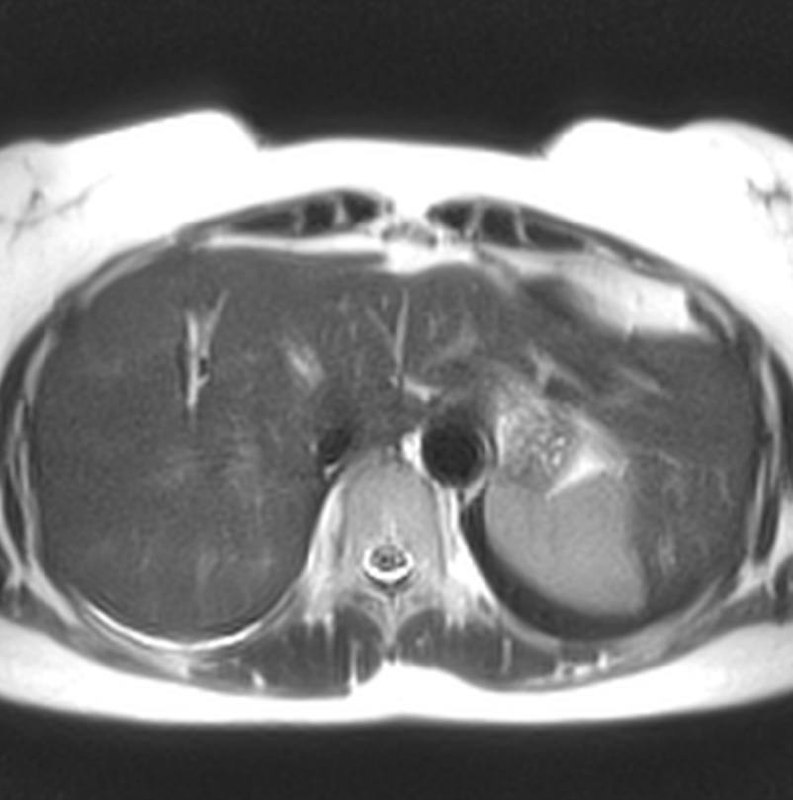

40 лет.

Думаю, что рак в хвосте панкреас, с вот такими метастазами в печень.

Ну, или и в панкреас тоже метастаз, хотя, других опухолей в животе не обнаруживается.